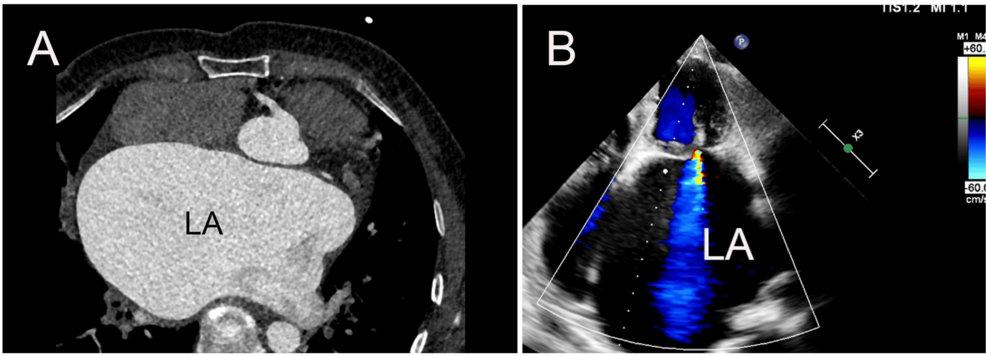

Mitral bioprosthetic valve replacement is a life-saving procedure for many patients with mitral valve disease. However, even with successful surgery, the risk of thromboembolic events – strokes, systemic emboli – remains. **Left atrial thrombosis** (LAT), the formation of blood clots within the left atrium, is a particularly dangerous complication. Unlike clots forming elsewhere in the circulatory system, LAT can be ‘silent’ – meaning they don’t cause immediate symptoms until they break loose and travel to vital organs. The case report by Curet underscores the potential for rapid, massive clot formation even with seemingly adequate, but ultimately suboptimal, anticoagulation.

• Advanced Imaging Techniques: Transesophageal echocardiography (TEE) remains the gold standard for detecting LAT, but its use is often limited to patients with specific symptoms. Future advancements in imaging, potentially including more sensitive TEE protocols or novel imaging modalities, could enable more routine and proactive screening.